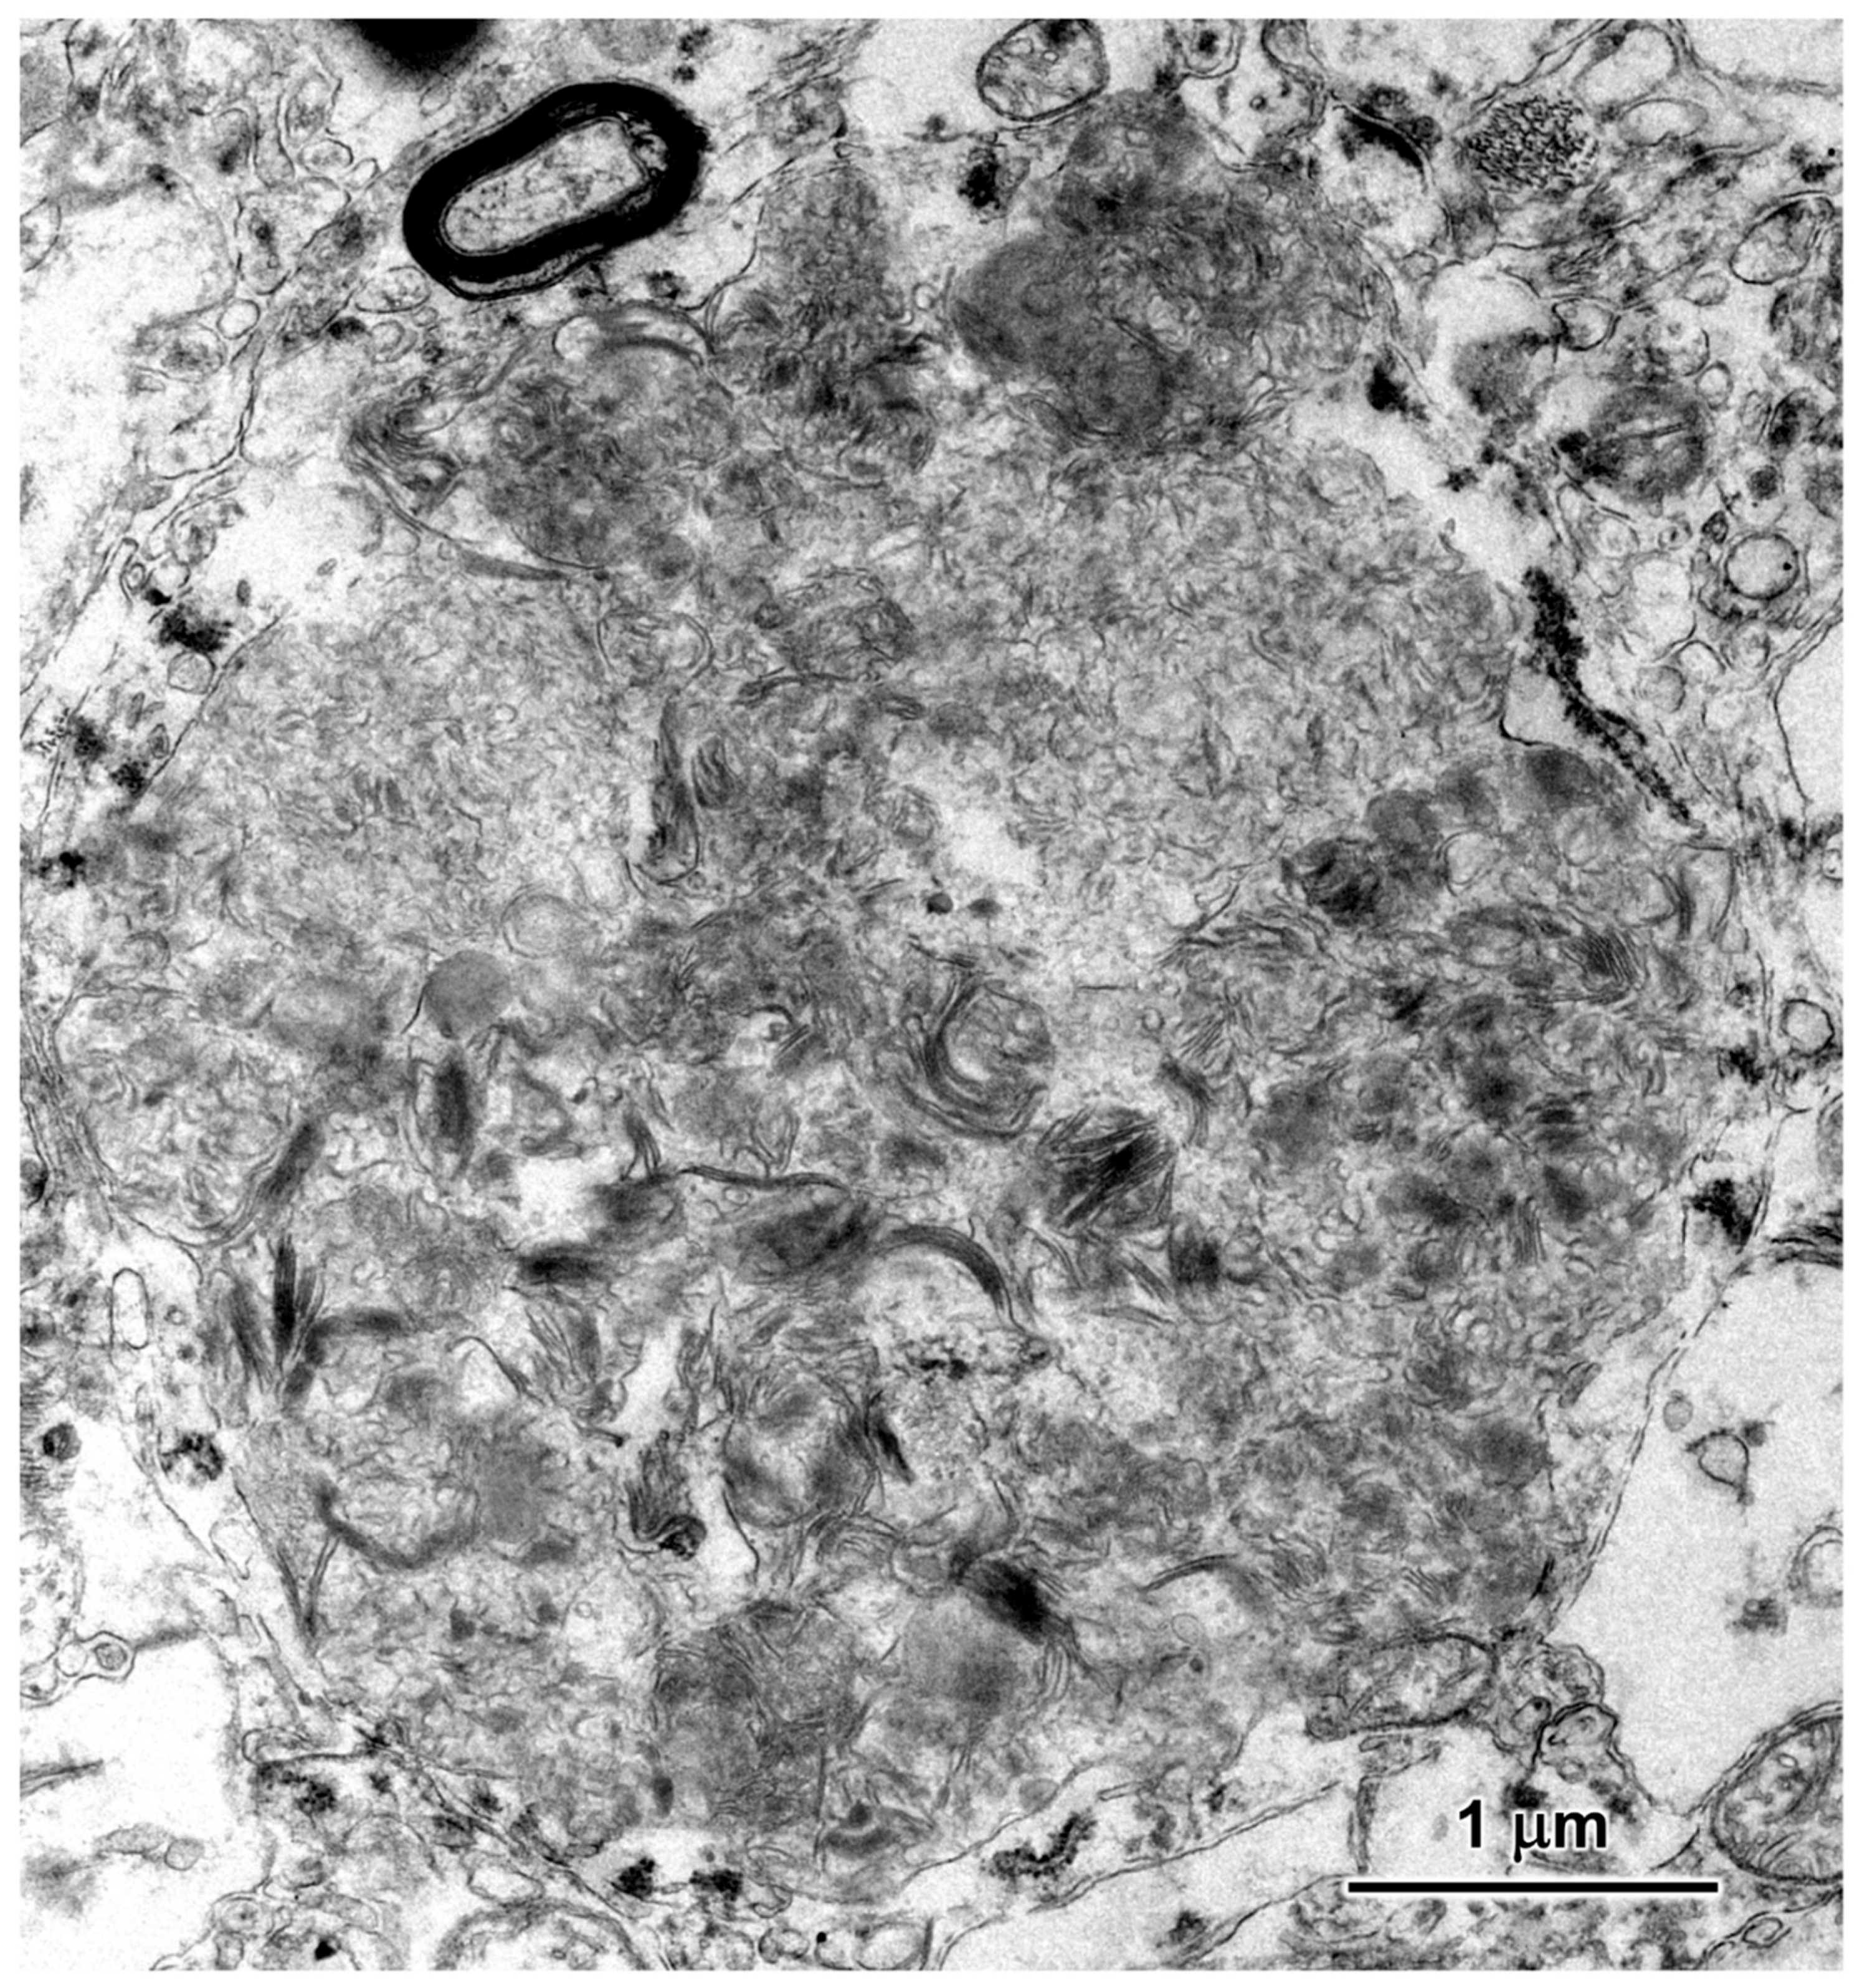

3.2. Microscopic Findings